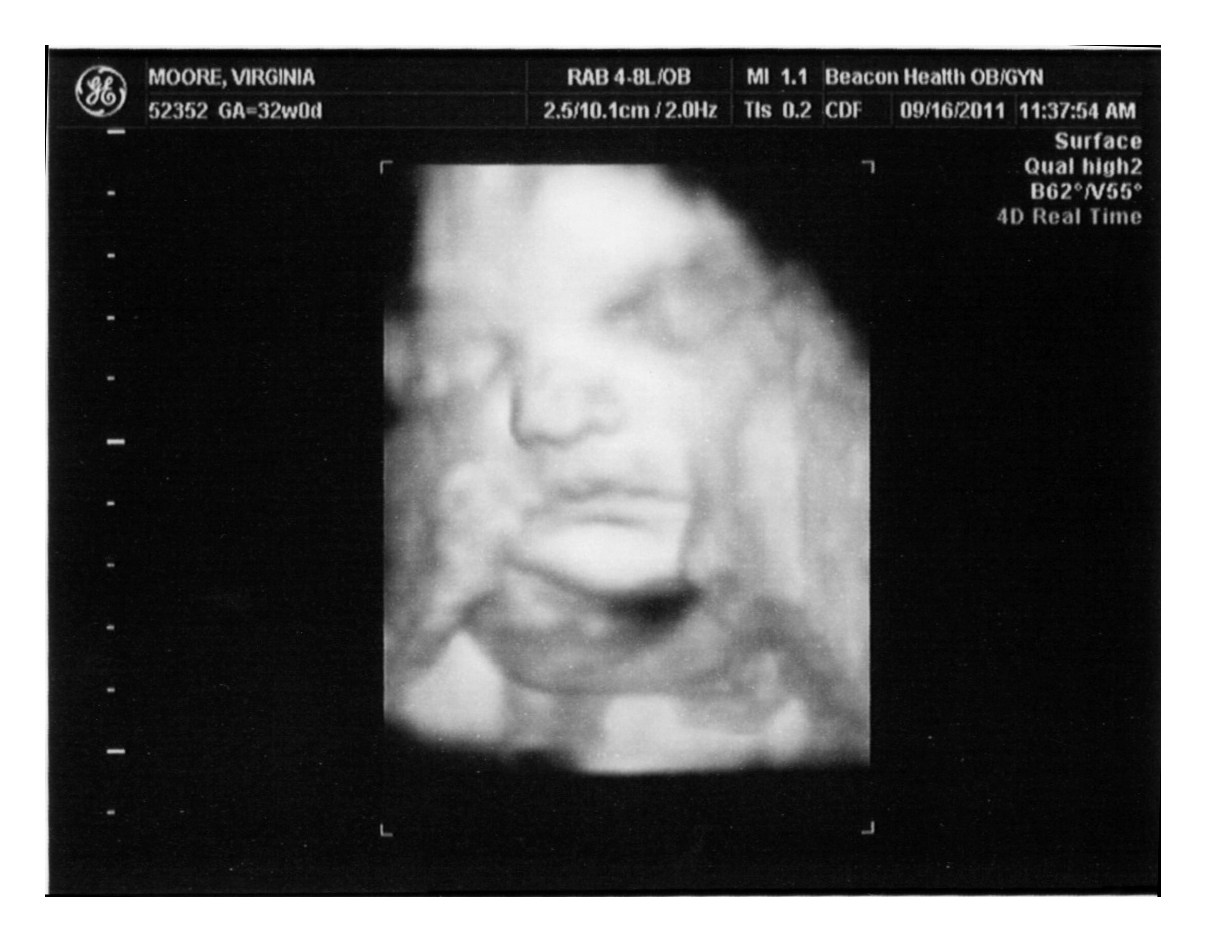

3d Ultrasound Of Our Little Man The Moberg Family